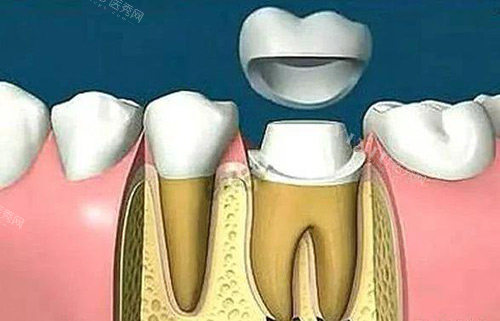

一、根管治疗后,牙齿为什么会变脆?

核心结论:根管治疗去除了牙髓(含血管和神经),牙齿失去营养供应,质地逐渐变干、变脆,咬硬物时易发生隐裂或折裂。

1. 牙齿的“营养来源”:牙髓是关键

天然牙的强度依赖牙髓提供的营养:

血管:运输水分和矿物质,保持牙体湿润

神经:感知压力,避免过度受力

根管治疗后,牙髓被清除,牙齿失去“营养补给”,逐渐脱水变脆,抗折能力下降约60%。

2. 牙齿结构的“天然弱点”:后牙更危险

后牙(如磨牙)承担主要咀嚼功能,牙体结构复杂:

窝沟点隙:易残留食物,增加咬合压力

根管系统:多根管设计导致牙体剩余量减少

统计显示,根管治疗后的后牙,未戴冠者3年内折裂率高达45%。